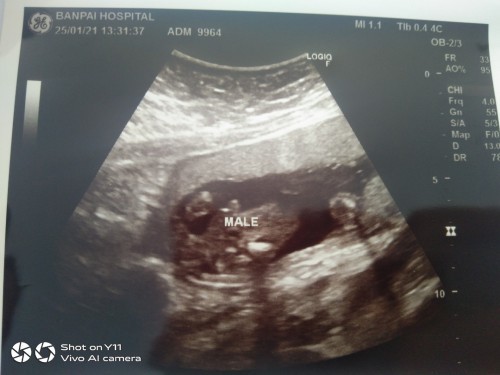

ชายค่ะ กำหนดคลอด17มีนาครับ❤️👶🏻